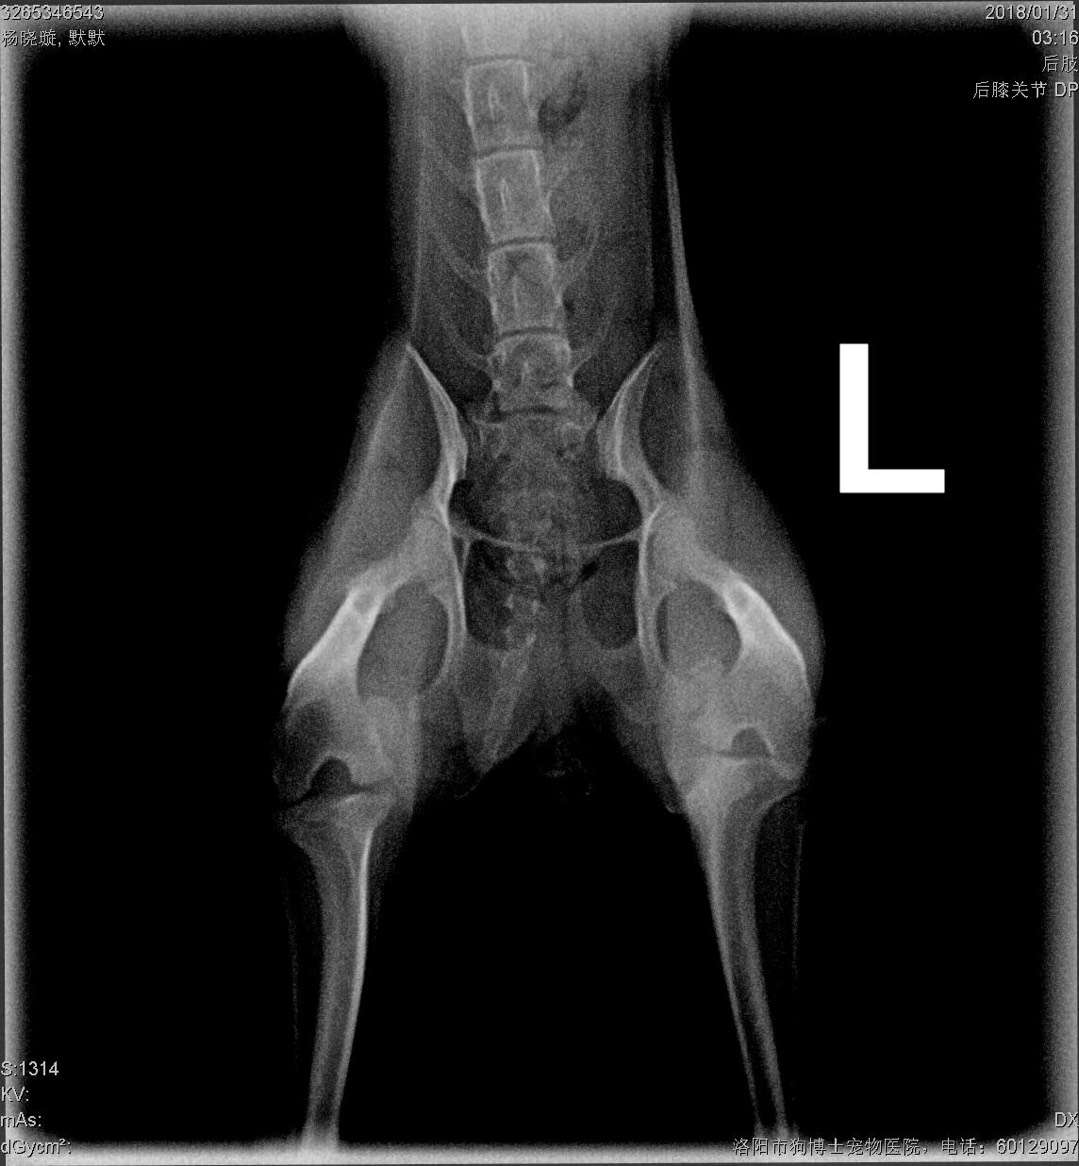

微茶髕骨移位手術一例:微茶妹妹,雙側(cè)髕骨3級移位移位,同時實施滑車溝再造術、脛骨粗隆移位術、及髕骨周圍軟組織修復術。手術期間,呼吸麻醉,心電監(jiān)護,手術持續(xù)2小時,一切順利,住院護理中。